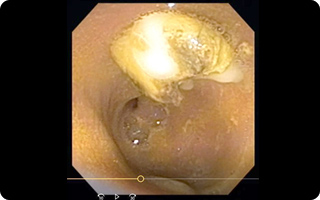

消化器科

違和感を覚えるほどの食べむらや下痢・嘔吐などが見られたら、消化器系の病気かもしれません。食べること、フンやおしっこをすることは命に関わります。必要に応じて、食事内容の指導から超音波や内視鏡を用いた高度な診療まで可能ですので、なんでもご相談ください。動物達が元気に楽しく食べてしっかりと用を足せるように、心を込めてサポートいたします。

来院の際は、吐物や下痢便など、ラップ等にくるんでご持参いただくと診断の助けになることがあります。